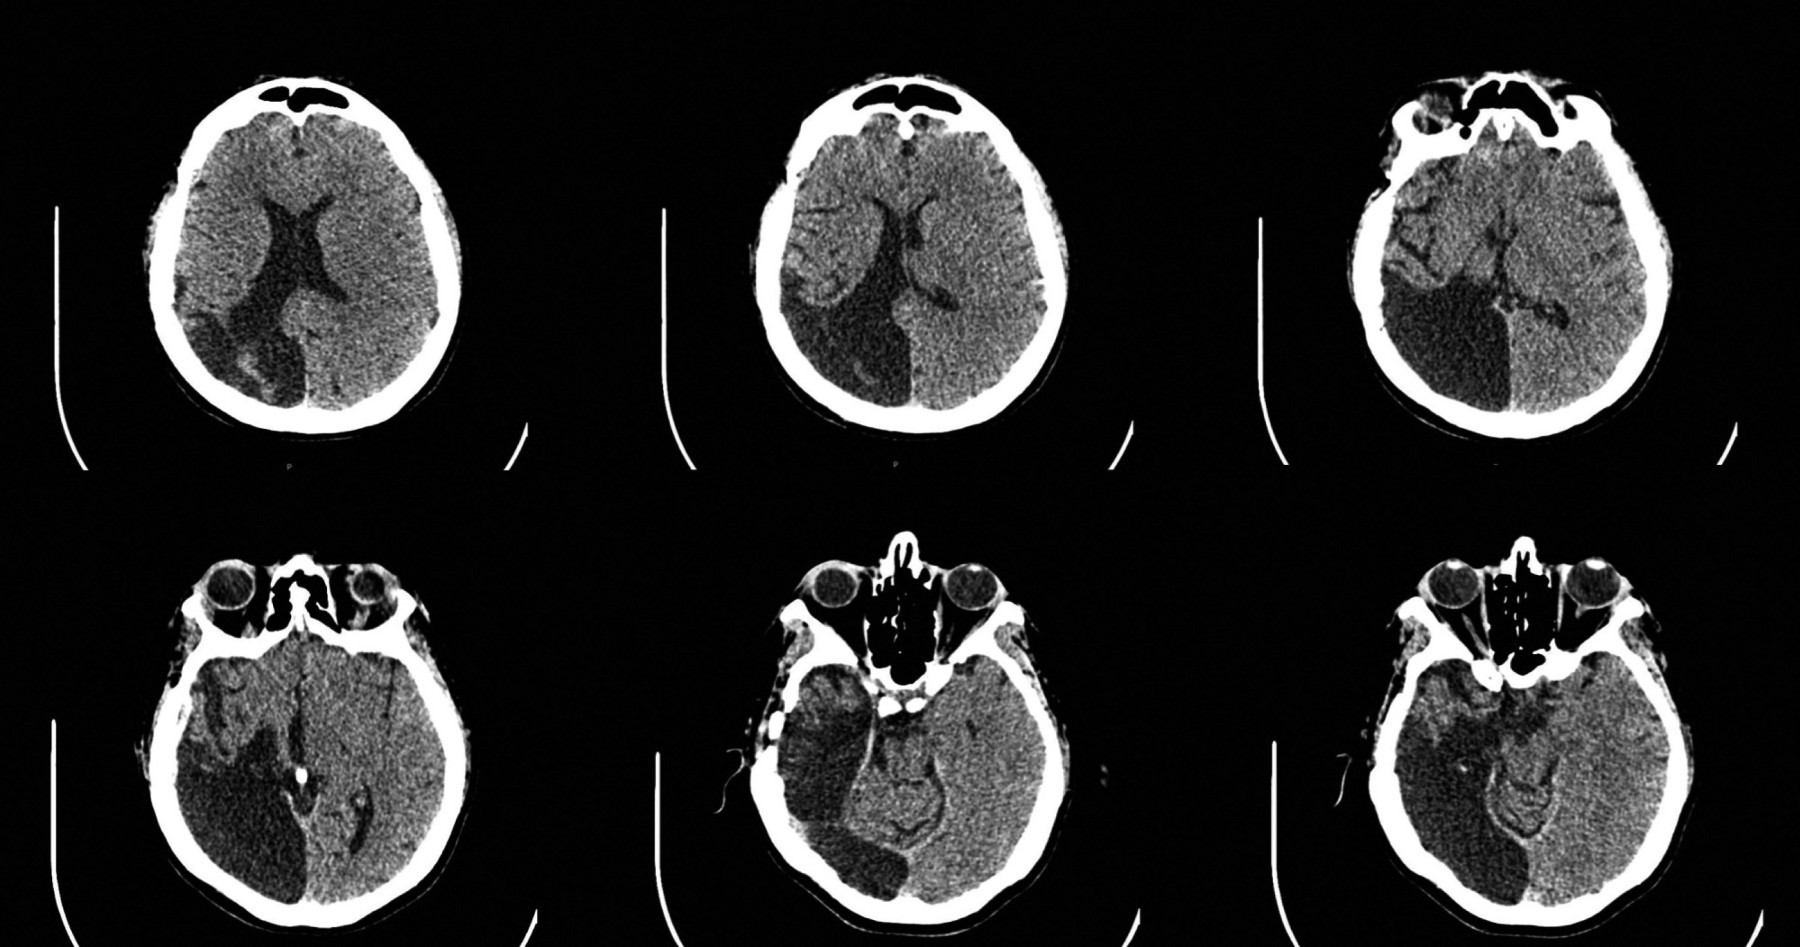

Una revisión sistemática realizada por Calle-López y colaboradores en la que se analizaron 77 episodios de 65 pacientes, mostró que la NF fue desencadenada en su mayoría por fármacos anticrisis (FAC) en 48.5% de los casos, principalmente levetiracetam, seguido de cirugía de la epilepsia en 31.8%, y 13.6% relacionada con la estimulación del nervio vago. En nuestra paciente, adicional a la cirugía de epilepsia, la presencia de un infarto de la arteria cerebral derecha (Figura 1) es un cofactor adicional que favoreció la aparición tardía de la NF, ya que se ha reportado la presencia de trastornos psicóticos de 4.67 a 5.05% en pacientes con evento cerebrovascular.5

Figura 1